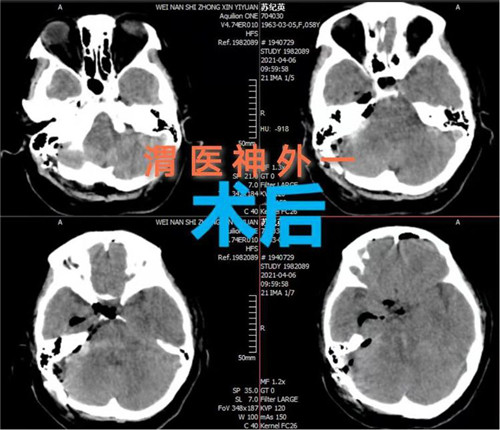

手术计划制定后,即刻安排手术,手术麻醉科确定了由麻醉医师钟永慧、配合护师党海婷和马丹组成的麻醉护理团队。手术历时近4个小时,手术过程患者生命体征平稳,术中总出血量约50毫升,术后患者恢复自主呼吸。术后次日患者生命体征平稳,意识恢复,右侧肢体活动正常,左侧肢体活动正在恢复中。

脑干出血病死率和致残率较高。因为脑干的生命中枢功能及其位置深、体积小的特点,脑干手术一直被视为手术禁区,术中稍有不慎将造成严重神经障碍,甚至死亡。此次手术的成功实施,是市中心医院神经外科一病区医生们挑战手术禁区,勇攀技术高峰,守护患者生命中枢的充分体现。